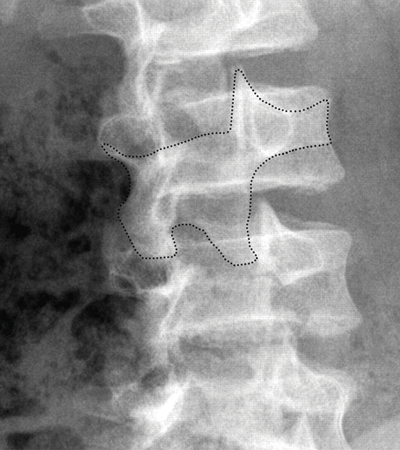

A spondylolysis is a defect of the pars interarticularis of the vertebral arch in lumbar vertebrae (most commonly L5 but it can happen more proximally too), so check out this x-ray and see if you can see my friend Spondi on this oblique view of the L-Spine:

So here are some times. Spondi faces the side of the x-ray (which is relative to the patient) so the dog in the x-ray above is facing to the patients left. The gots eyes are the pedicles, the collar is the par interarticularis and it will be more radiolucent with separation, and his nose the transverse process. Pretty cool huh?!